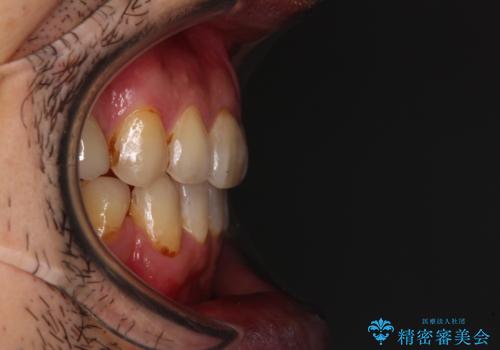

- むし歯による奥歯の痛みを気にして来院された患者様です。

神経にまでむし歯の及んでいる歯や、既に根管治療がされている歯に痛みがあったため、まずは根管治療を行うこととしました。

その後、以前行った抜歯矯正の後戻りをインビザライン・ライトにより改善し、むし歯や銀歯はオールセラミッククラウンにて補綴治療することとしました。

痛みは速やかに引き、銀歯や黒く変色したむし歯がセラミッククラウンで自然な色合いに仕上がり、患者様には大変満足していただきました。